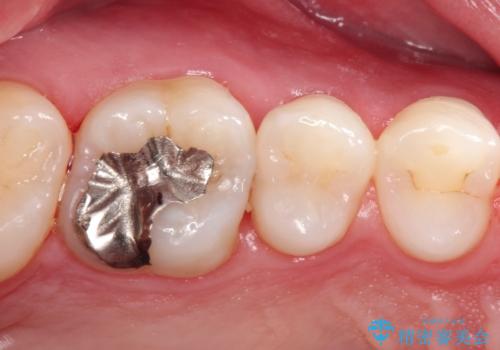

【セラミックインレー】定期検診にて虫歯を発見

- 定期検診にて虫歯を発見したため、セラミッククラウン、セラミックインレーにて治療を行いました。

小臼歯の虫歯は歯髄に近かったため、部分的断髄法にて歯髄を部分的に保存した治療をおこなっています。